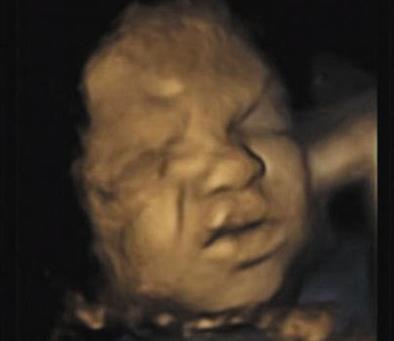

被宝宝四维彩超丑哭是怎么回事 胎儿四维

637x400 - 218KB - PNG

拍四维彩超时胎儿的搞怪表情图,难道在

394x341 - 9KB - JPEG

宝宝能睁开眼睛吗,照的四维彩超宝宝好像睁

429x288 - 12KB - JPEG